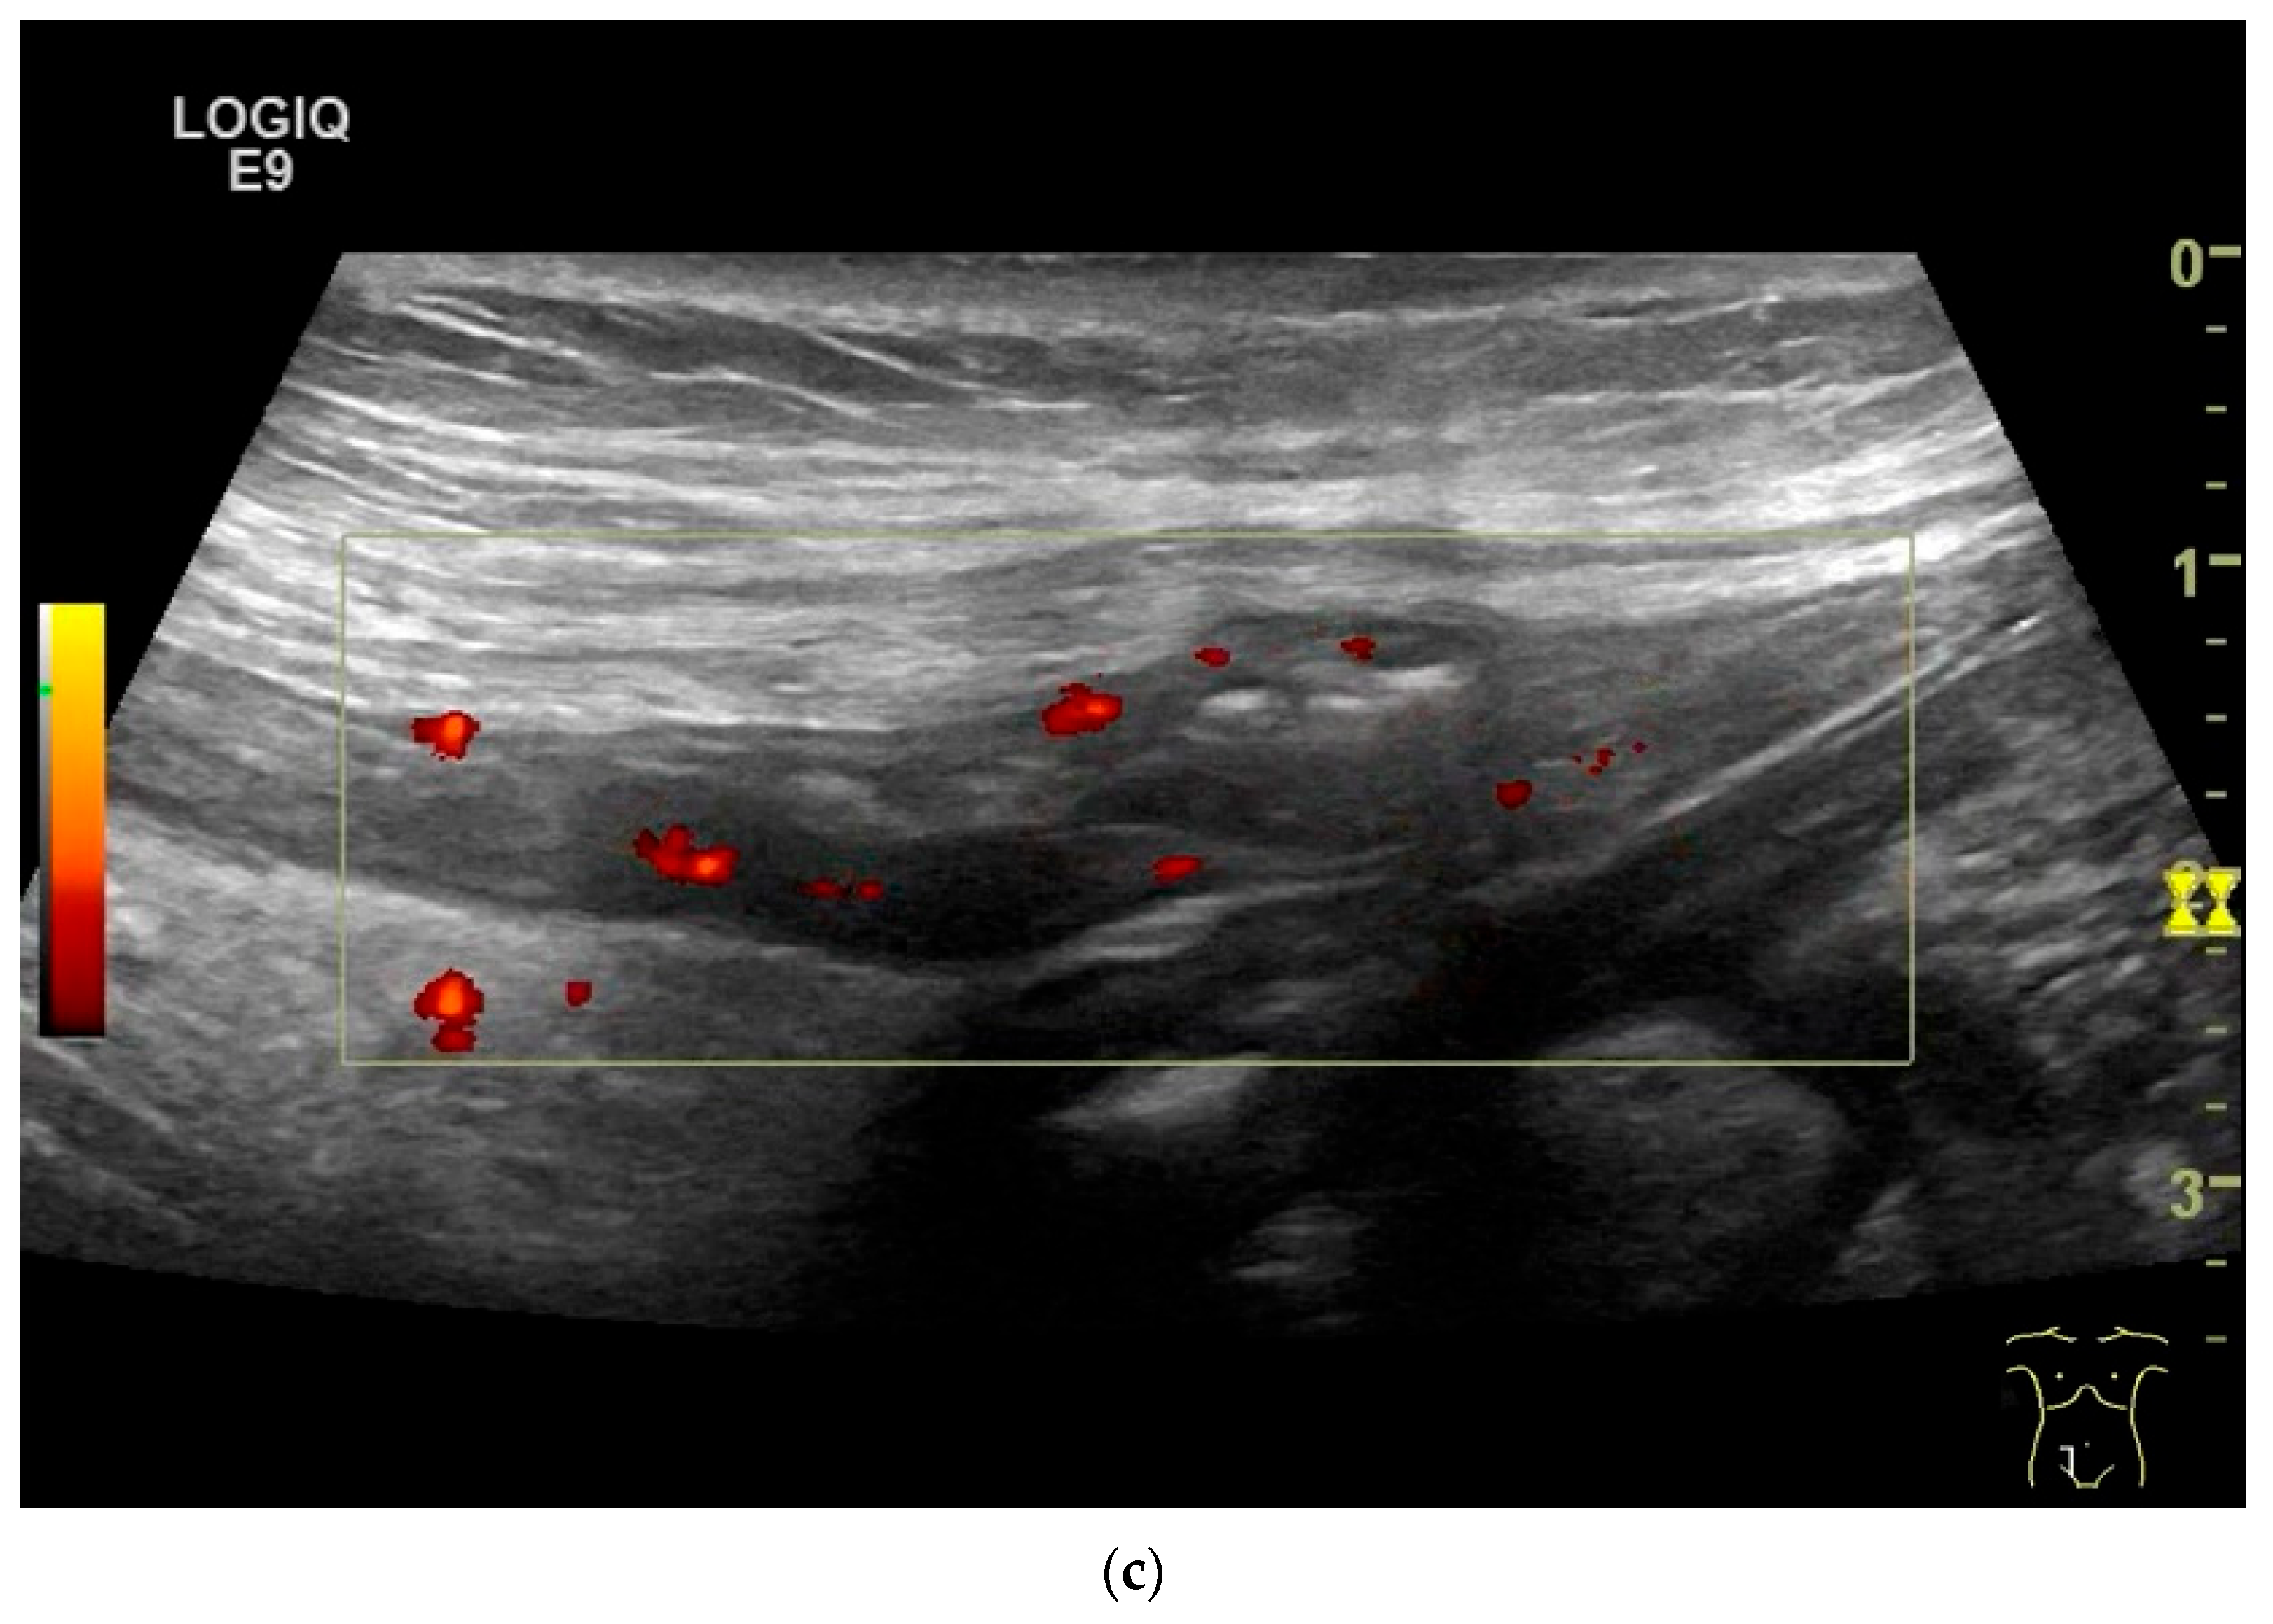

| Lymphoma | Very pronounced wall thickening with marked hypoechogenicity. Large regional and distant lymph nodes. Look for splenic infiltration. Tumor vessels on CDI and hyperenhancement on CEUS. Heterogeneous hyperechogenicity of the mesentery with walling of the mesenteric vessels. Multiple localizations are possible. |

| GIST | Round hypoechoic masses, homogeneous or heterogeneous depending on size. They usually originate from the muscularis propria, which can be difficult to distinguish in US. Small vessels on CDI, hyperenhancement on CEUS. They move with the small intestine and can change position. |

- Multiparametric US, including CDI and CEUS, enhances lesion characterization by assessing vascularity and necrosis, especially in GISTs and neuroendocrine tumors.